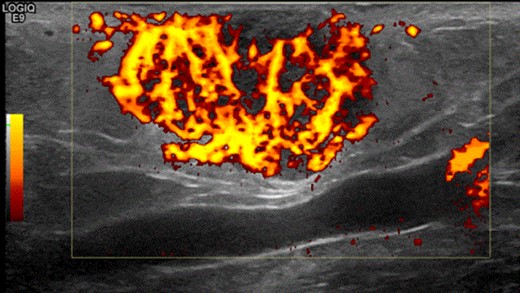

A 63-year-old woman presented to vascular clinic with a large, painless, exophytic erythematous and centrally indurated lesion of the left arm (Fig. 1). Having grown rapidly over the preceding few months and due to recurrent episodes of bleeding, it was investigated in the community by ultrasound. Due to sonographic features of hypervascularity it was presumed to be a haemangioma and referred onto our service (Fig. 2). Her past medical history was significant for hypertension, being an ex-smoker, chronic obstructive pulmonary disease (COPD) and cancer of the left breast that had been treated with wide-local excision, axillary lymph node clearance and chemotherapy 6 years prior to this presentation.

Shows the highly vascularized sonographic features of the mass on ultrasound scan.